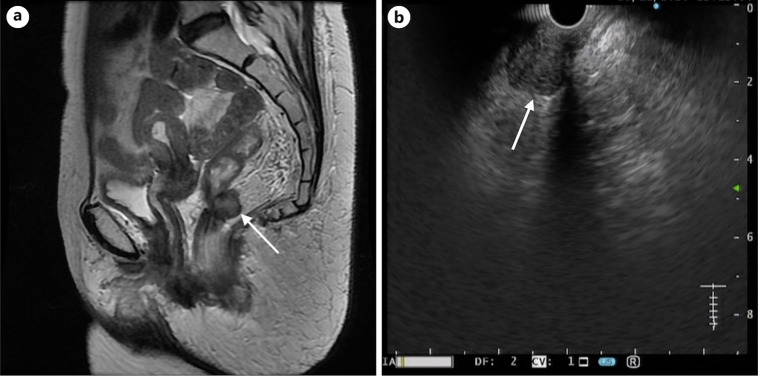

Case presentations: We report 8 cases of suspected locoregional tumor growth (LRTG) on MRI: adjacent or in the rectal wall, within the mesorectal fascia, high presacral region, and obturator foramen. MRI images were studied thoroughly before and during EUS to identify the target lesion using rectal EUS-FNA. Patients were prepared using an enema. The procedure was performed on an outpatient basis without conscious sedation. FNA was performed using a 25G needle. The patient received a 3-day course of ciprofloxacin after the procedure to prevent infection of the perirectal space. Identification of the target was the most difficult part of EUS but was successful in all cases. FNA revealed adenocarcinoma in 7 cases. Five cases were confirmed by TME results: 1 patient died before the operation, and 1 patient was treated with CRT. One patient with a suspected node in the obturator foramen was free of tumors on FNA. The TME resection specimen contained 31 lymph nodes without metastasis. All procedures were well tolerated, and no complications were observed.

Abstract Image